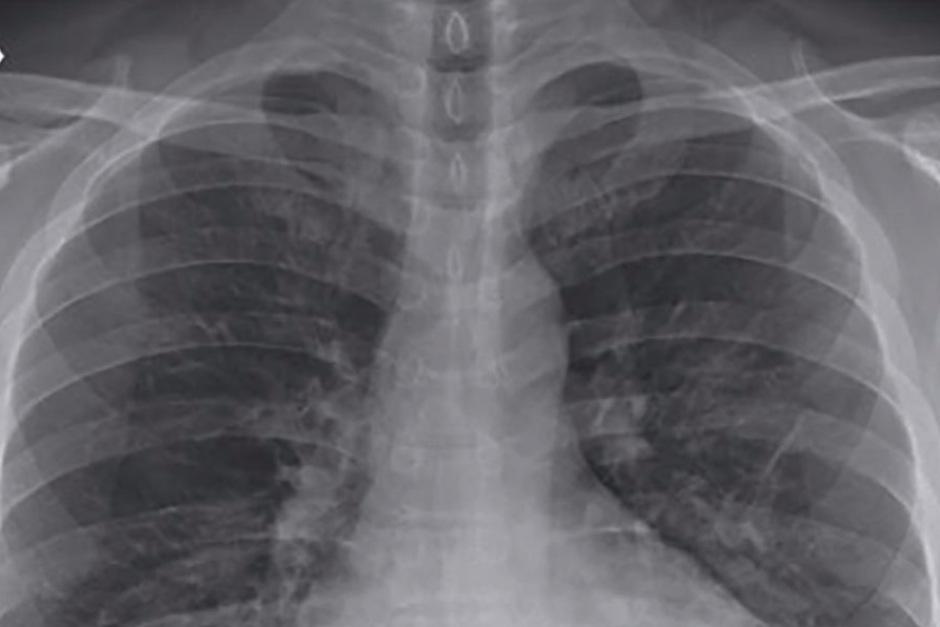

La autopsia no encontró virus en su hígado, corazón, intestino, piel o médula ósea, pero sí apareció coronavirus en su tejido pulmonar, que, pese a que la paciente no mostraba síntomas, presentaba los daños habituales de una infección vírica.

Los autores propusieron llevar a cabo lavados bronqueoalveolares, es decir, insertar suero limpiador en los pulmones, antes de dar de alta a los pacientes para garantizar la detección de virus ocultos, aunque se trata de un procedimiento más complejo, costoso y largo que los test con hisopos.